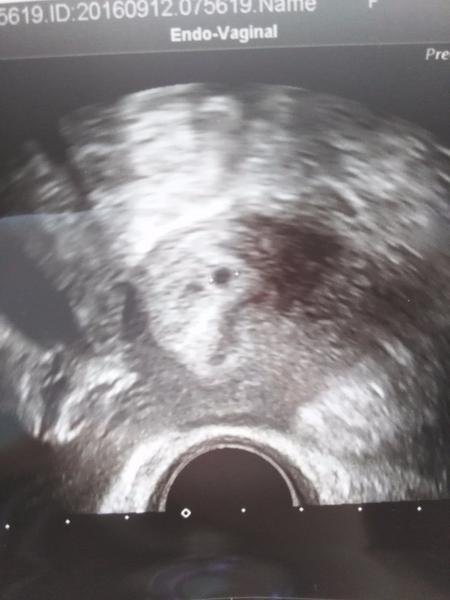

Holky vidíte některá ducha? Mám 4

dny před MS a už to nemůžu vydržet a zkouším testovat...